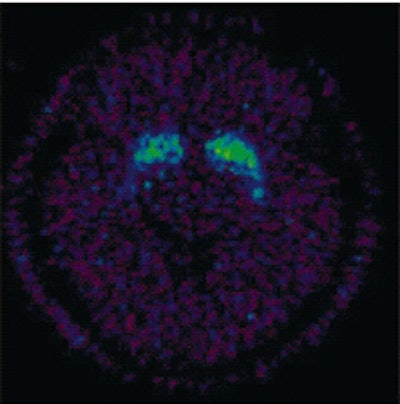

![]() |

The 11C-raclopride binding potential images at the level of the striatum for one participant during meditation (above) and during the speech (below). 11C-raclopride binding potential in ventral striatum is evidence of increase endogenous dopamine release during meditation.

According to the results, there was a significant decrease (7.9%) in BP in the ventral striatum. During active meditation, the participants reported a significant decrease in their readiness for action (p<0.05) along with heightened sensory imagery (p<0.05).

"The major finding of the present study has been the demonstration of increased dopaminergic tone in the ventral striatum during an altered conscious state...the fact that the ventral striatum was the only region in which the decrease in dopamine receptor availability reached statistical significance is of interest. Two of the three front-subcortical circuits regulating behavior include structures in the ventral striatum," the authors explained.